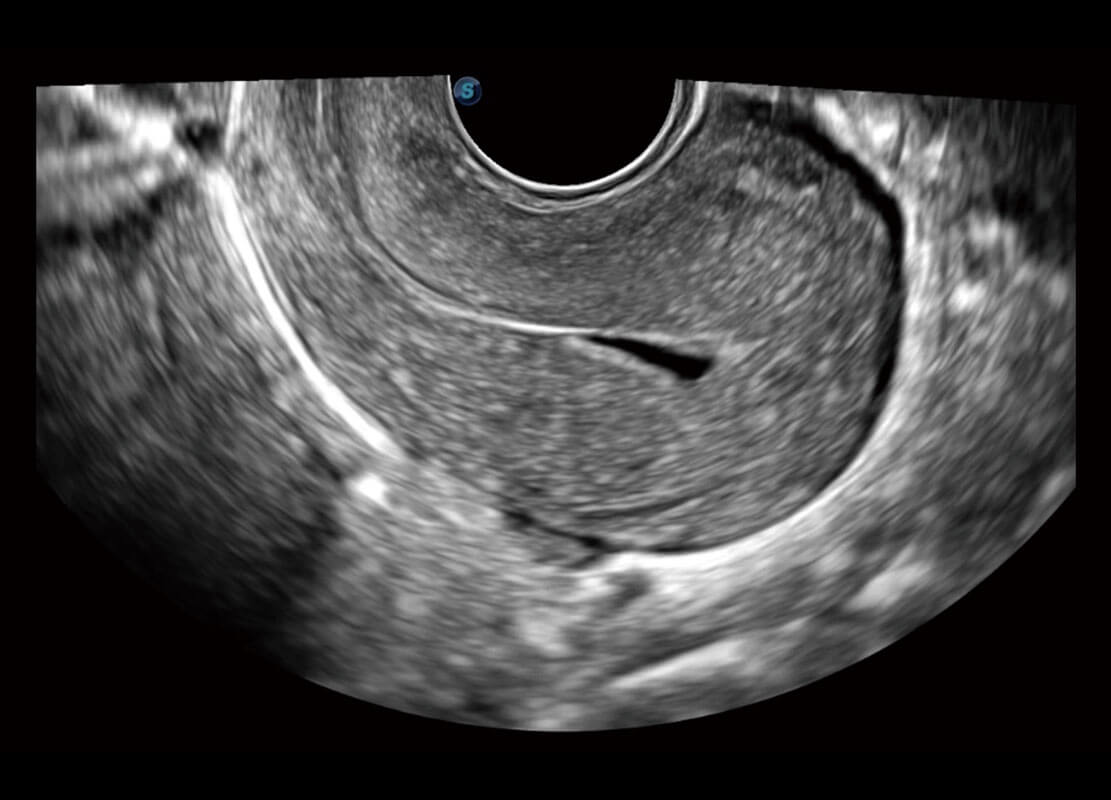

腔内妇科-宫腔分离

腔内妇科-卵巢

P60优异的图像质量搭载专科探头,在妇科基础疾病的诊断、卵泡生长的监测、输卵管通畅情况的判别等方面为您提供生殖应用方案。